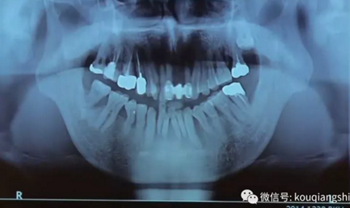

我們可以看到#17,18的牙周炎非常嚴(yán)重

從CT上我們可以看到骨破壞非常嚴(yán)重

拔牙后也將拔牙窩內(nèi)的黏膜提拉上來(lái)

十周之后我們可以看到黏膜組織沒(méi)有出現(xiàn)凹陷

翻瓣之后可以看到形成的充足的骨量